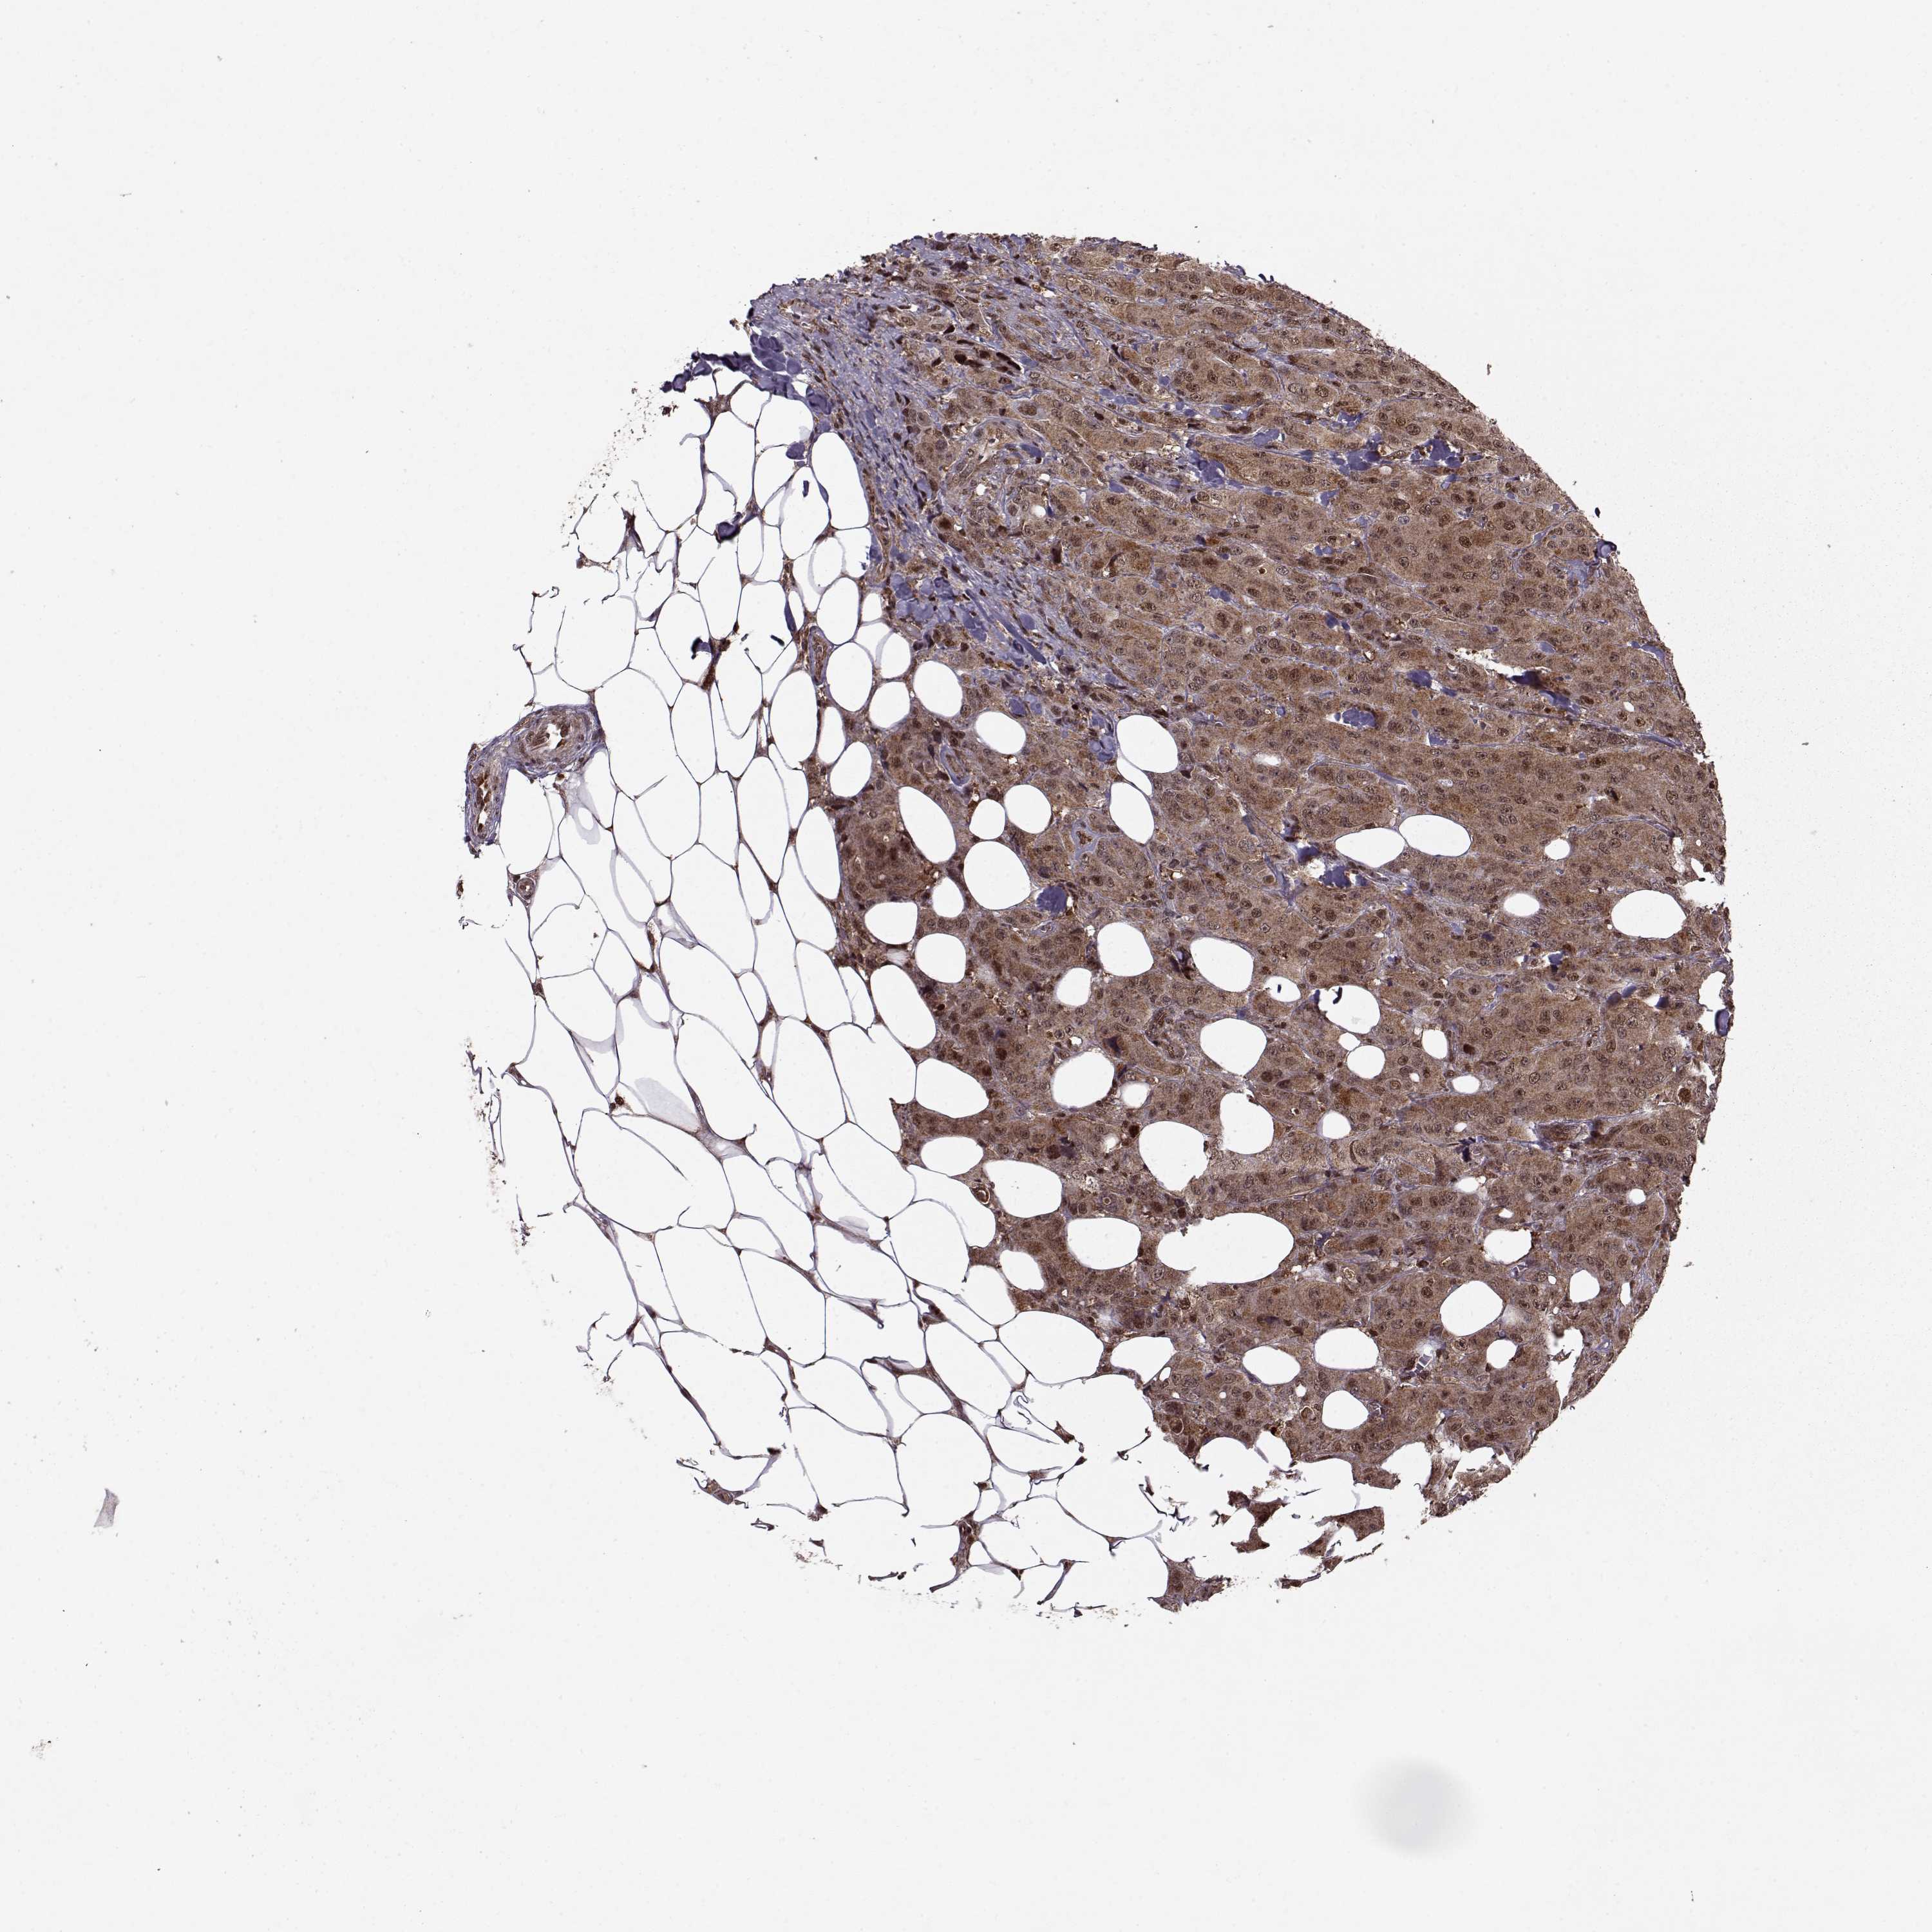

CANCER BREAST CANCER Show tissue menu

BRCA TCGA BRCA VALIDATION PROTEIN EXPRESSION

ANTIBODIES

AND

VALIDATION